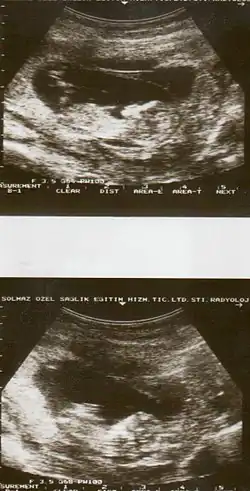

Ultrasound showing placental abruption

Placental abruption is suspected when a pregnant mother has sudden localized abdominal pain with or without bleeding. The fundus may be monitored because a rising fundus can indicate bleeding. An ultrasound may be used to rule out placenta praevia but is not diagnostic for abruption.[8] The diagnosis is one of exclusion, meaning other possible sources of vaginal bleeding or abdominal pain have to be ruled out in order to diagnose placental abruption.[5] Of note, use of magnetic resonance imaging has been found to be highly sensitive in depicting placental abruption, and may be considered if no ultrasound evidence of placental abruption is present, especially if the diagnosis of placental abruption would change management.[16]